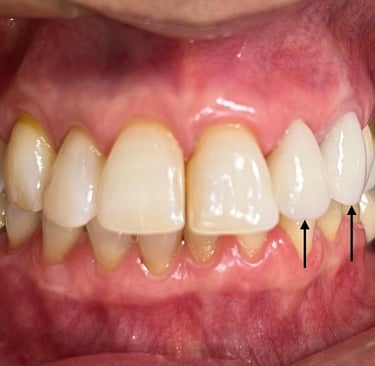

Coroas em Dissilicato de Lítio

Todos os caso a seguir estão associadas a clareamento dentário

Cirurgia de aumento de coroa clínica antes das coroas

Caso que demonstra a vantagem da integração de diversas áreas da odontologia, unindo cirurgia, periodontia, prótese e estética para alcançar resultados funcionais e harmônicos.

Antes

Depois